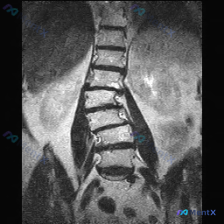

只看这张腰椎MRI冠状位,除了明显的侧弯,还有两个容易漏的关键发现

整理到一张腰椎MRI T2加权序列冠状位的影像资料,先不看后续的其他序列和临床信息,只看这张图的话,有几个点比较值得拿出来讨论: 1. 脊柱力线确实有明显异常,侧弯方向和顶端位置也比较清楚 2. 椎间盘的信号和椎间隙高度有非对称性改变 3. 扫描野里除了腰椎,还能看到双侧肾脏,肾盂肾盏区似乎有信号变...

整理了一张腰椎MRI T2序列冠状位图像的资料,大家可以先看看核心影像表现: - 腰椎整体向右侧凸(凸向右侧,凹向左侧) - 各椎体高度大致正常,边缘可见骨赘形成 - 腰椎下段(L4-L5、L5-S1)椎间隙不对称,凹侧更紧凑 - 冠状位上左侧下方椎间孔区域脂肪信号略显模糊,空间受限 没有提供患者的...

整理到一份腰椎MRI-T2冠状位的影像资料,第一眼就能看到明确的脊柱侧弯——腰椎呈C型向左侧凸。 但仔细看还有几个点: 1. 侧弯凸侧(右侧)椎体边缘有不同程度骨赘形成 2. 双侧小关节增生明显,关节周围有高信号 3. 椎间隙左右不对称,凹侧(左侧)椎间孔空间看起来受压缩 4. 目前层面没看到明确的...

网上看到一份腰椎MRI T2序列冠状位的影像资料,先抛出来和大家讨论一下读片思路。 影像里看到的主要信息整理了一下: - 脊柱序列:腰椎生理曲度轻度侧弯,凸向左侧,各椎体排列基本连续,没看到明显滑脱错位 - 椎体与骨髓:各腰椎椎体形态大致规则,边缘有轻度骨质增生;骨髓T2信号均匀高信号,没看到明显异...